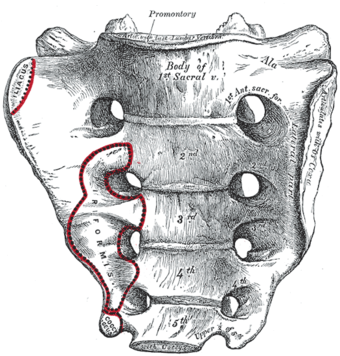

العجز، السطح الحوضي. | |

في البشر، العجز sacrum ( []ˈsækrəm[] أو []ˈseɪkrəm[]; مفرده: sacrums أو sacra)، هي عظام كبيرة، مثلثة الشكل، تقع على قاعدة العمود الفقري وعلى الجزء العلوي، الخلفي لتجويف الحوض، حيث تكون مغروزة مثل الوتد بين عظام الورك. الجزء العلوي منها تتصل بالفقرة القطنية، والجزء السفلي منها متصلة بالعصعص. عادة، يبدأ العجز كفقرة خامسة غير ملتحمة تبدأ بالالتحام في عمر 16-18 سنة وعادة ما يكتمل التحامها كعظمة واحدة في الرابعة والثلاثين.